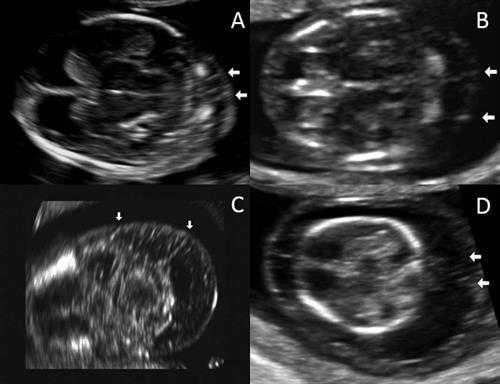

Исследователи ретроспективно просмотрели электронные истории болезни 3275 пациенток, которые проходили скрининг первого триместра и затем рожали в женском отделении Техасского Детского Госпиталя между ноябрем 2011 и декабрем 2014 года. Они характеризовали септы как тонкие линейные эхогенные структуры в воротниковом пространстве плода, которые располагались между кожей плода и нижерасположенными тканями. Кроме того, наличие септ и расширенного воротникового пространства расценивалось как кистозная гигрома.

УЗ изображения воротниковых перегородок в поперечном срезе. А) воротниковое пространство 2.3 мм. В) 4 мм. С) 5.2мм. D) 8мм. Все изображение предоставлены the Journal of Ultrasound in Medicine.